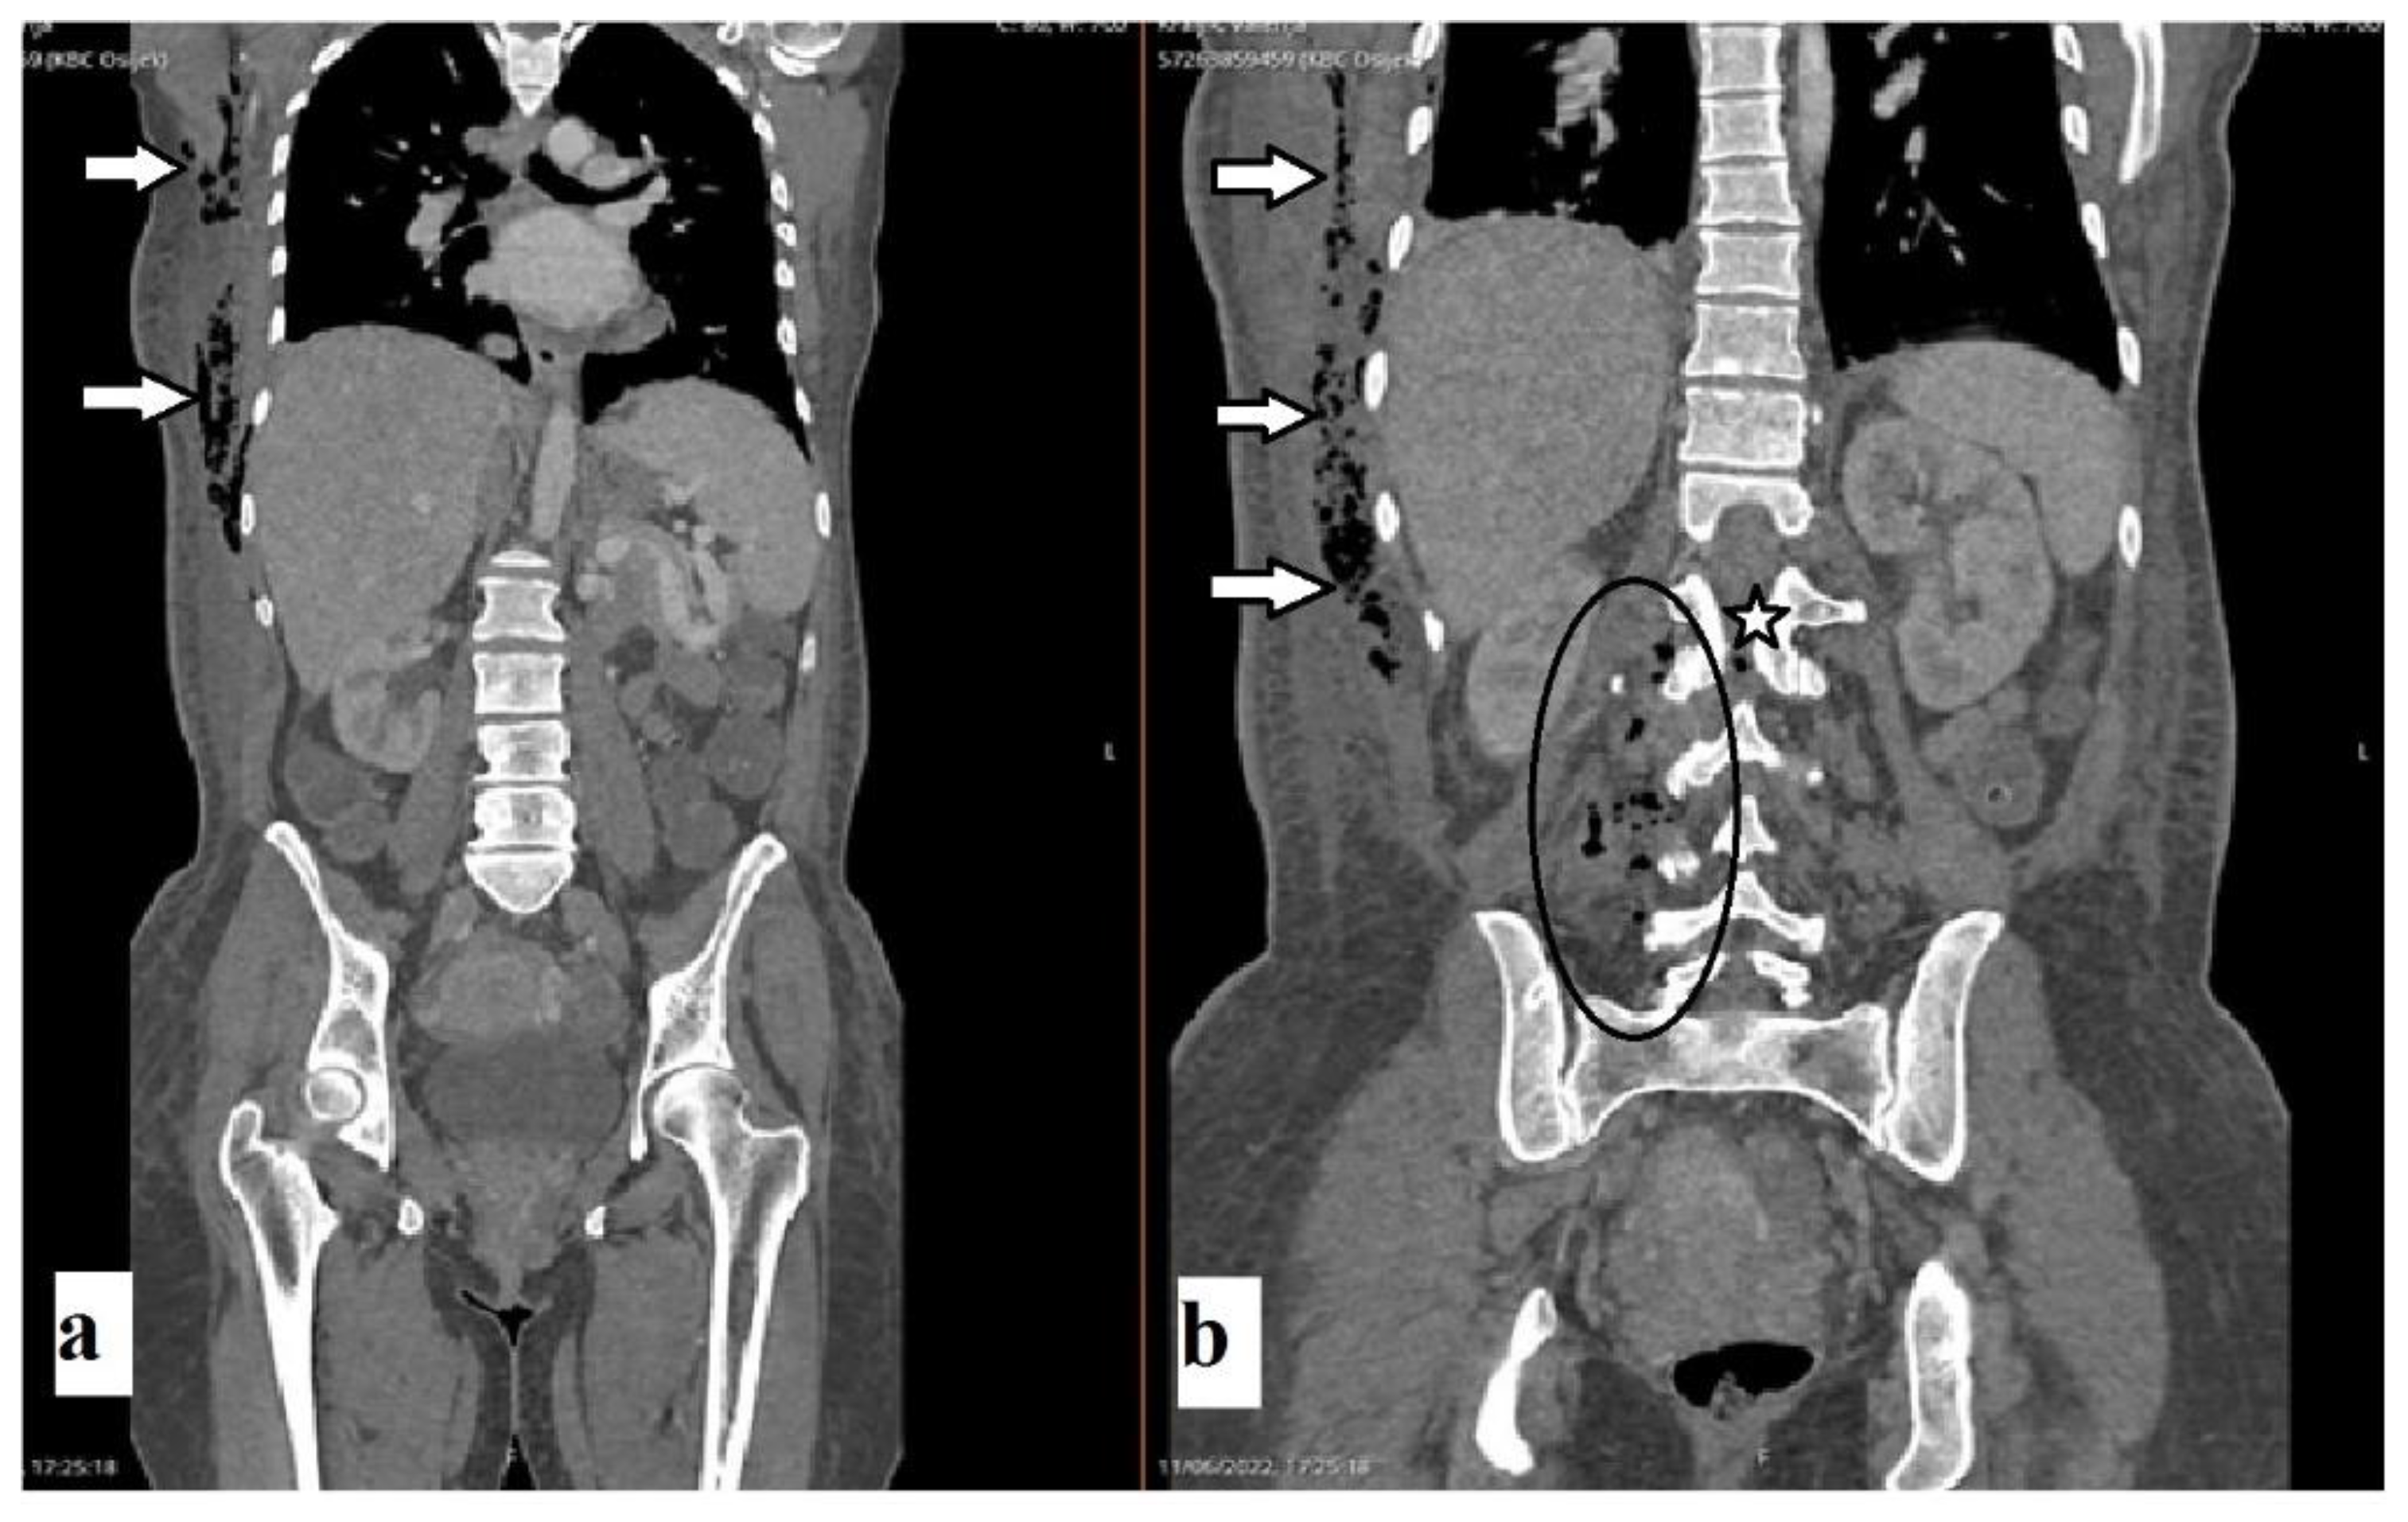

A 43-year-old female patient was admitted to the Department of Neurosurgery, University Hospital Center, Osijek, due to lumbar pain and L3 radiculopathy. Symptoms were first presented ten days before admission, and the patient underwent symptomatic therapy at a local hospital. Despite therapy, the symptoms persisted, and a computed tomography (CT) scan of the whole spine was obtained on the day of admission at another hospital. The right-sided gas inclusions were presented along the cervical, thoracic, and lumbar paravertebral muscles, with the largest collection at the segments of the L3 and L4 vertebra. Moreover, the purulent spondylitis of the L3 vertebra was noted with concomitant purulent epidural content and gas inclusion (Figure 1). Additionally, a CT scan of the brain revealed pneumocephalus: multiple gas inclusions along the left-sided brain hemisphere and at the skull base (Figure 2). According to her medical history, she had a history of previous COVID-19 infection, and she did not receive the SARS-CoV-2 vaccine. Additionally, she had a history of unspecified cardiomyopathy for which the patient did not provide an explanation, nor were there detailed medical records pertaining to this comorbidity. A physical examination of the patient revealed that the key muscle strength assessment of the right lower limb was 3/5 and for the left lower limb was 4+/5, respectively. No other chronic or familiar diseases were found via interview or from the medical records. The patient was disoriented upon admission, and her Glasgow Coma Scale (GCS) score was 12 (eyes 3, verbal response 4, motor response 5). Based on the clinical findings as well as radiologic imaging, she underwent urgent surgery, which was performed with local anesthesia in a regular fashion. The anesthesiologist was reluctant to perform endotracheal anesthesia due to the intraoral condition of the patient, carious teeth, and the assumed duration of the surgery, which lasted up to ten minutes. Upon skin incision and soft tissue preparation, the fascia was incised, and the subfascial space was opened. The drainage was placed along the right-sided paravertebral muscles at the level of L3 and L4 vertebrae and left in situ for the next three weeks. Despite the clinical condition of our patient, she was not hospitalized in the intensive care unit (ICU).

Figure 1. Non-enhanced coronal CT scans of the abdomen, thorax, and spine (a,b) revealed axillar and paracostal gas inclusions (arrows). Scans revealed paravertebral abscess (b) and gas inclusions at the level of L3 (oval) and gas inclusion in the spinal canal (star).